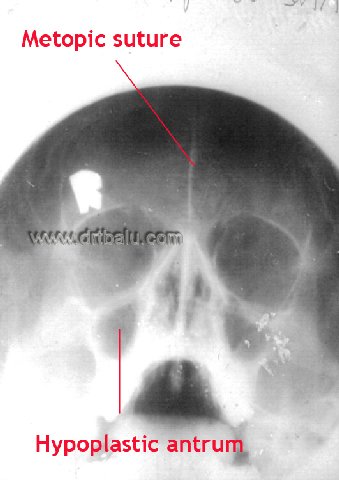

In x ray para nasal sinuses waters view the normal frontal sinus margins show scalloping. Loss of this scalloping is a classic feature of frontal mucocele. If frontal sinus is congenitally absent (agenisis) then a suture line known as the metopic suture is visible in the fore head area. Sometimes a pair of large anterior ethmoidal air cells may take up the place of frontal sinuses. Here too the metopic suture line is visible. This suture divides the two halfs of frontal bone of the skull in infants and children. This suture line usually disappears at the age of 6 when it fuses. If this suture is not present at birth it will cause a keel shaped deformity of the skull (trigonocephaly).

X-ray PNS showing metopic suture

Since hypoplastic antra are associated with sclerosis of its margins, it will be very difficult to perforate the medial wall of the antrum while performing antrostomy.